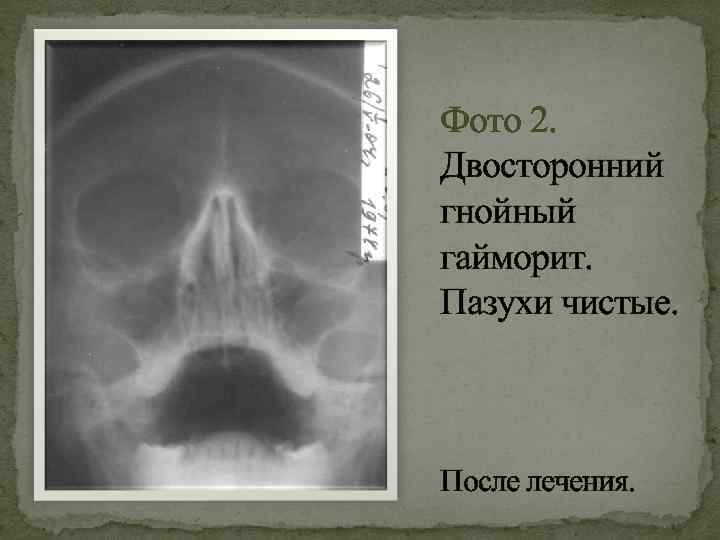

КТ-снимки хронического этмоидита: подробная визуализация